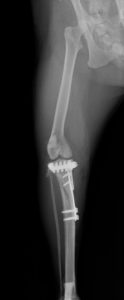

TTA

膝蓋骨靭帯の付着部(脛骨粗面)を骨きりして前方に持ち上げることで、大腿部の筋肉(大腿四頭筋)の角度を変え、大腿四頭筋群の作用によって正常な関節の動きを再現します。専用のTTAプレートと脛骨粗面を持ち上げておくためのケージを設置します。

32kg ラブラドール